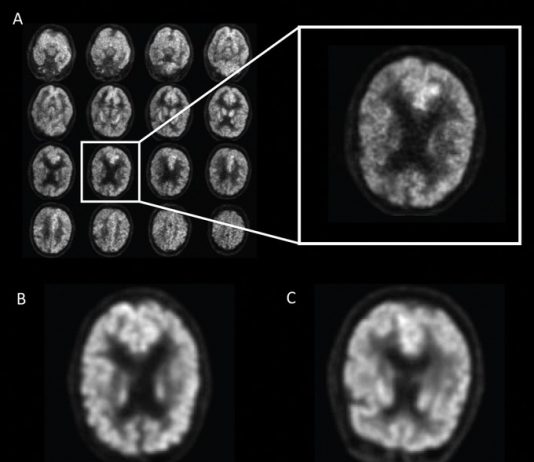

전 세계에서 수천만 명이 앓고 있지만 조기 진단이 어려운 알츠하이머병을 인공지능(AI)으로 조기에 진단하는 데 성공했다.캘리포니아대학 샌프란시스코 캠퍼스(UCSF) 방사선 의학영상 진단학과 손재호 박사 연구팀이 뇌 스캔을 이용한 딥러닝 훈련을 실시한 결과, 40건의 사례에서 알츠하이머 치매 조기 진단에 성공했다고 발표했다.연구 결과는 국제적인 의학저널인 '방사선학(Radiology)' 6일자에 논문 ‘A Deep Learning Model to...